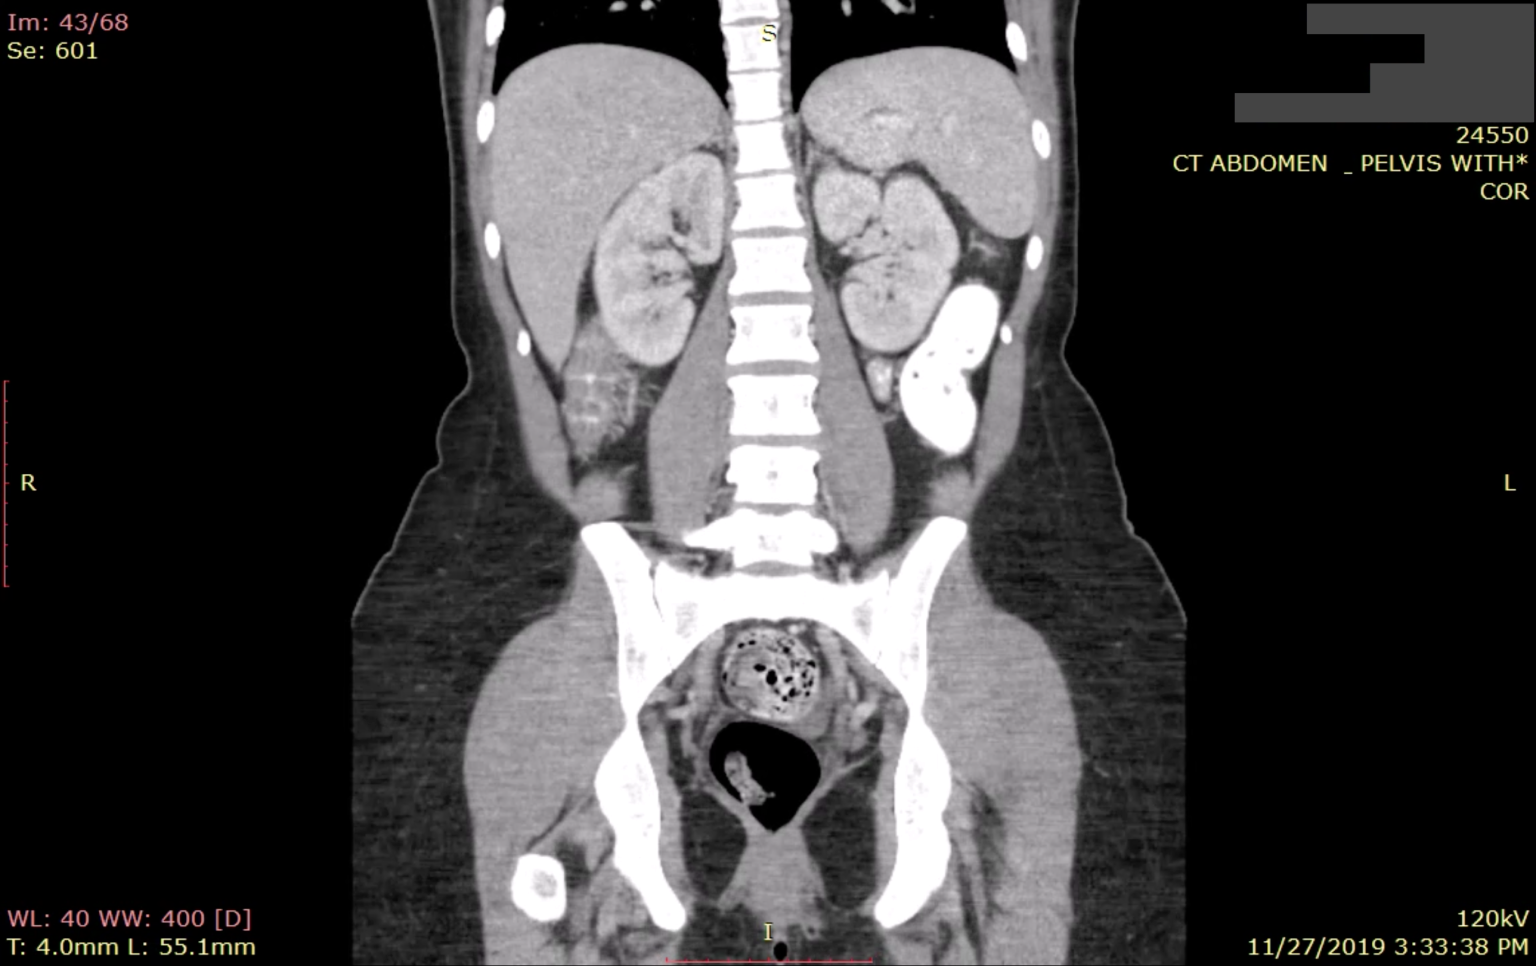

Greenbone è una azienda specializzata in sicurezza delle reti e gestione delle vulnerabilità. Nel Settembre 2019 ha pubblicato uno studio sulla sicurezza del sistema PACS, (Picture Archiving and Communication System), uno dei sistemi maggiormente usati per lo storage di immagini diagnostiche in ambito sanitario. Già nel primo stadio dello studio la situazione si mostrava estremamente grave, con oltre 600 server PACS raggiungibili da chiunque con ricerche tramite comuni motori di ricerca come Google. Questi 600 server sparsi nel mondo contenevano oltre 733 milioni di immagini, delle quali 400 milioni circa visualizzabili e persino scaricabili. I dati esposti riguardavano circa 24.3 milioni di persone.

Qualche mese dopo Greenbone effettuò una seconda verifica, trovando addirittura una situazione peggiorata: da 733 milioni di immagini esposte, in pochi mesi si era passati a 1 miliardo e 190 milioni di immagini. Il 60% in più. In conseguenza di questa grave situazione, Greenbone ha avvisato le autorità nazionali dei singoli stati riguardo la problematica, invitando ad una immediata messa in sicurezza di server e dati.

A riconferma del problema portiamo anche una testimonianza pubblicata dalla testata Techcrunch: nel mese di Novembre Lucas Lundgren, ricercatore di sicurezza svedese, ha dimostrato alla redazione della testata come fosse possibile, in pochissimi minuti, individuare il database esposto di uno dei più grandi ospedali di Los Angeles, accedendo ai dati di decine di migliaia di persone (fortunatamente il server è stato messo in sicurezza dopo la segnalazione del problema). Ha inoltre spiegato come l'esposizione di tali dati renda molto semplice l'organizzazione di frodi assicurative e il furto d'identità, aggiungendo il fatto che, per alcuni, è persino possibile ricostruire uno storico delle condizioni di salute personali.